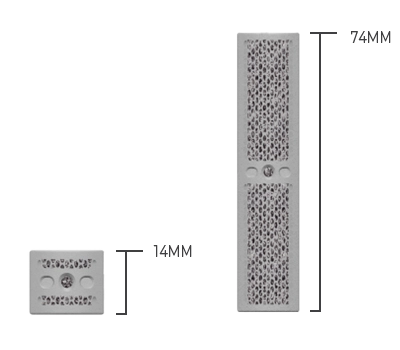

Height Options

Heights available in 14mm – SOmm (2mm increments}

Special order: heights 52mm – 74mm (2mm increments)